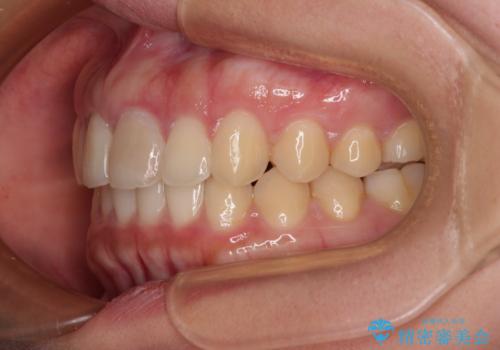

飛び出した上顎前歯 インビザラインで引っ込める

- 前歯の突出感を気にして来院された患者様です。

奥歯の咬み合わせは理想的な咬合に近く、インビザラインでも十分に対応できる歯列でした。

舌の突出癖を改善するためのトレーニングを行いつつ、上下歯列全体を後方に移動させ、更にはIPR(歯と歯の間を削る)によりスペースを獲得することで、口元の突出感を改善することとしました。